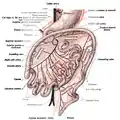

Diagram showing the small intestine and surrounding structures | |

Small intestine in situ, greater omentum folded upwards.